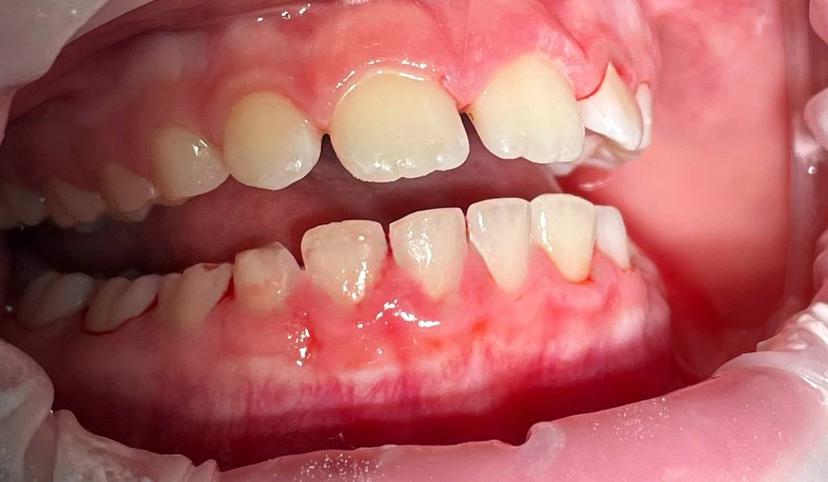

На прием обратились родителе с ребенком 14 лет с просьбой научить ребенка чистить правильно зубы. В ходе приема был проведен осмотр и обнаружено обильное количество как мягких зубных отложений так и твердых (зубной камень) Далее на все зубы был нанесен индикатор налета, для того чтобы показать и родителям и ребенку наглядно, именно те участки где хуже всего прочищает ребенок. Далее проведена профессиональная гигиена с помощью Air Flow и ультразвукового аппарата. После профессиональной гигиены полости рта были даны рекомендации, как улучшить гигиену в домашних условиях.

На прием обратились родителе с ребенком 10 лет с просьбой научить ребенка чистить правильно зубы. В ходе приема был проведен осмотр и обнаружено обильное количество как мягких зубных отложений так и твердых (зубной камень) Далее на все зубы был нанесен индикатор налета, для того чтобы показать и родителям и ребенку наглядно, именно те участки где хуже всего прочищает ребенок. Далее проведена профессиональная гигиена с помощью Air Flow и ультразвукового аппарата. После профессиональной гигиены полости рта были даны рекомендации, как улучшить гигиену в домашних условиях.